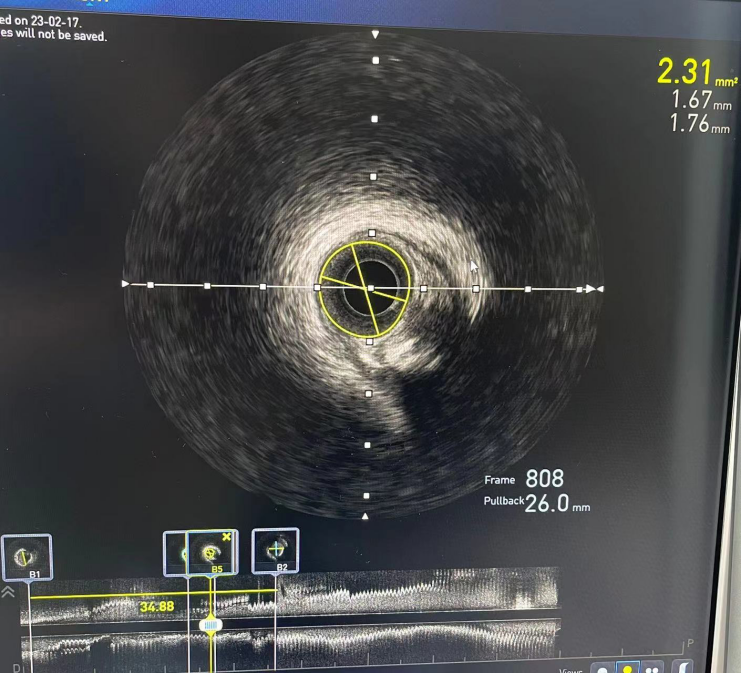

徐亚伟教授应用ETcath 200介入机器人对指引导管进行精准调整,使其到达冠状动脉口部,建立器械输送通路,并使用机器人的多种模式操作导丝,避免导丝进入分支,顺利将指引导丝推送至病变远端,应用机器人循导丝推送IVUS进行评估,测得管腔面积仅剩余2.31mm²。

术前IVUS图像